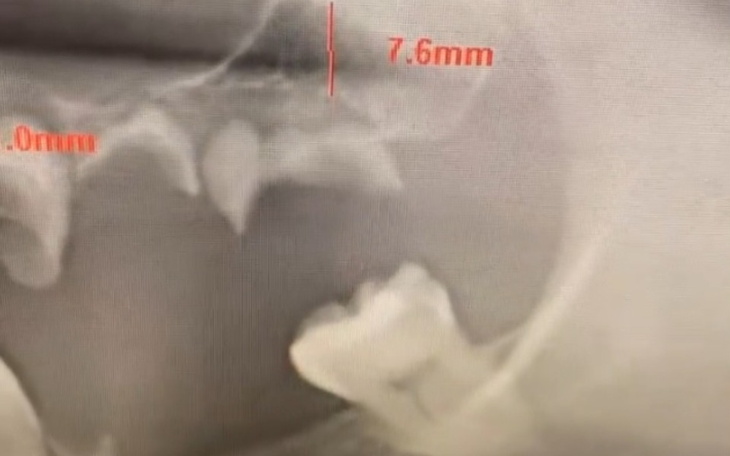

Witam od urodzenia genetycznie zmagam się z zdeformowaną rzuchwą, wymagana jest kosztowna operacja, niestety bez niej trudno będzie żyć, na codzień mierze się z bólem głowy, który promieniuje od rzuchwy, w przyszłości ciężko będzie nawet i spożywać posiłki, jest to moje marzenie, proszę o pomoc!